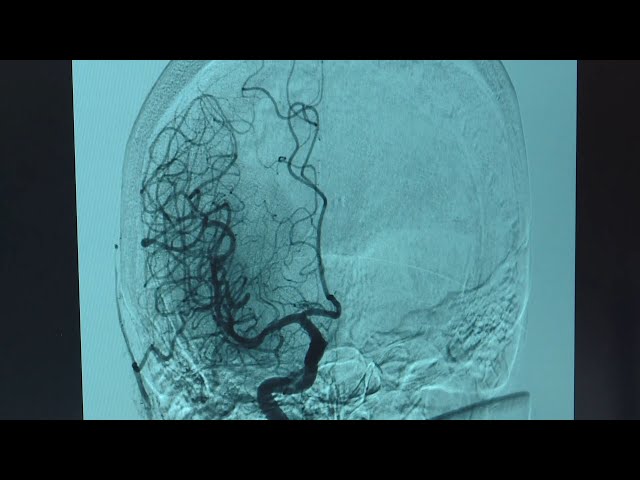

В сосудистом центре Ангарска медики провели две высокотехнологичные операции — помогли пациенту с ишемическим инсультом и удалили тромб в артерии головного мозга. Всё это стало возможным благодаря внедрению инновационных методов хирургического вмешательства.